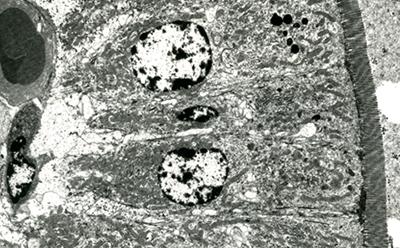

TEM sample prepared, cut and imaged during TEM course